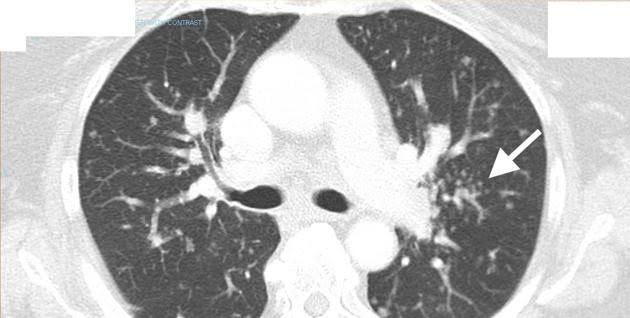

The so-called galaxy sign, initially described as the sarcoid galaxy, represents a coalescent granuloma seen in a minority of patients with pulmonary sarcoidosis . The same appearance can be seen in tuberculosis. In other words, it represents a mass-like region composed of numerous smaller granulomas. The appearance of a central core with peripheral nodules is reminiscent of a globular cluster or galaxy. Central cavitation does occur and the lesions may be surrounded by ground-glass opacity 4. The latter is thought to represent extensive interstitial sarcoid granulomas below the resolution of HRCT rather than alveolitis or hemorrhage